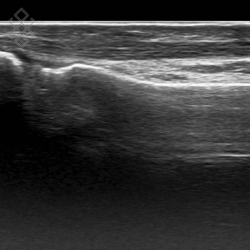

Échographie du Pied

La durée de l'examen est d'environ 20 minutes. Il est indolore et est réalisé par un médecin radiologue.